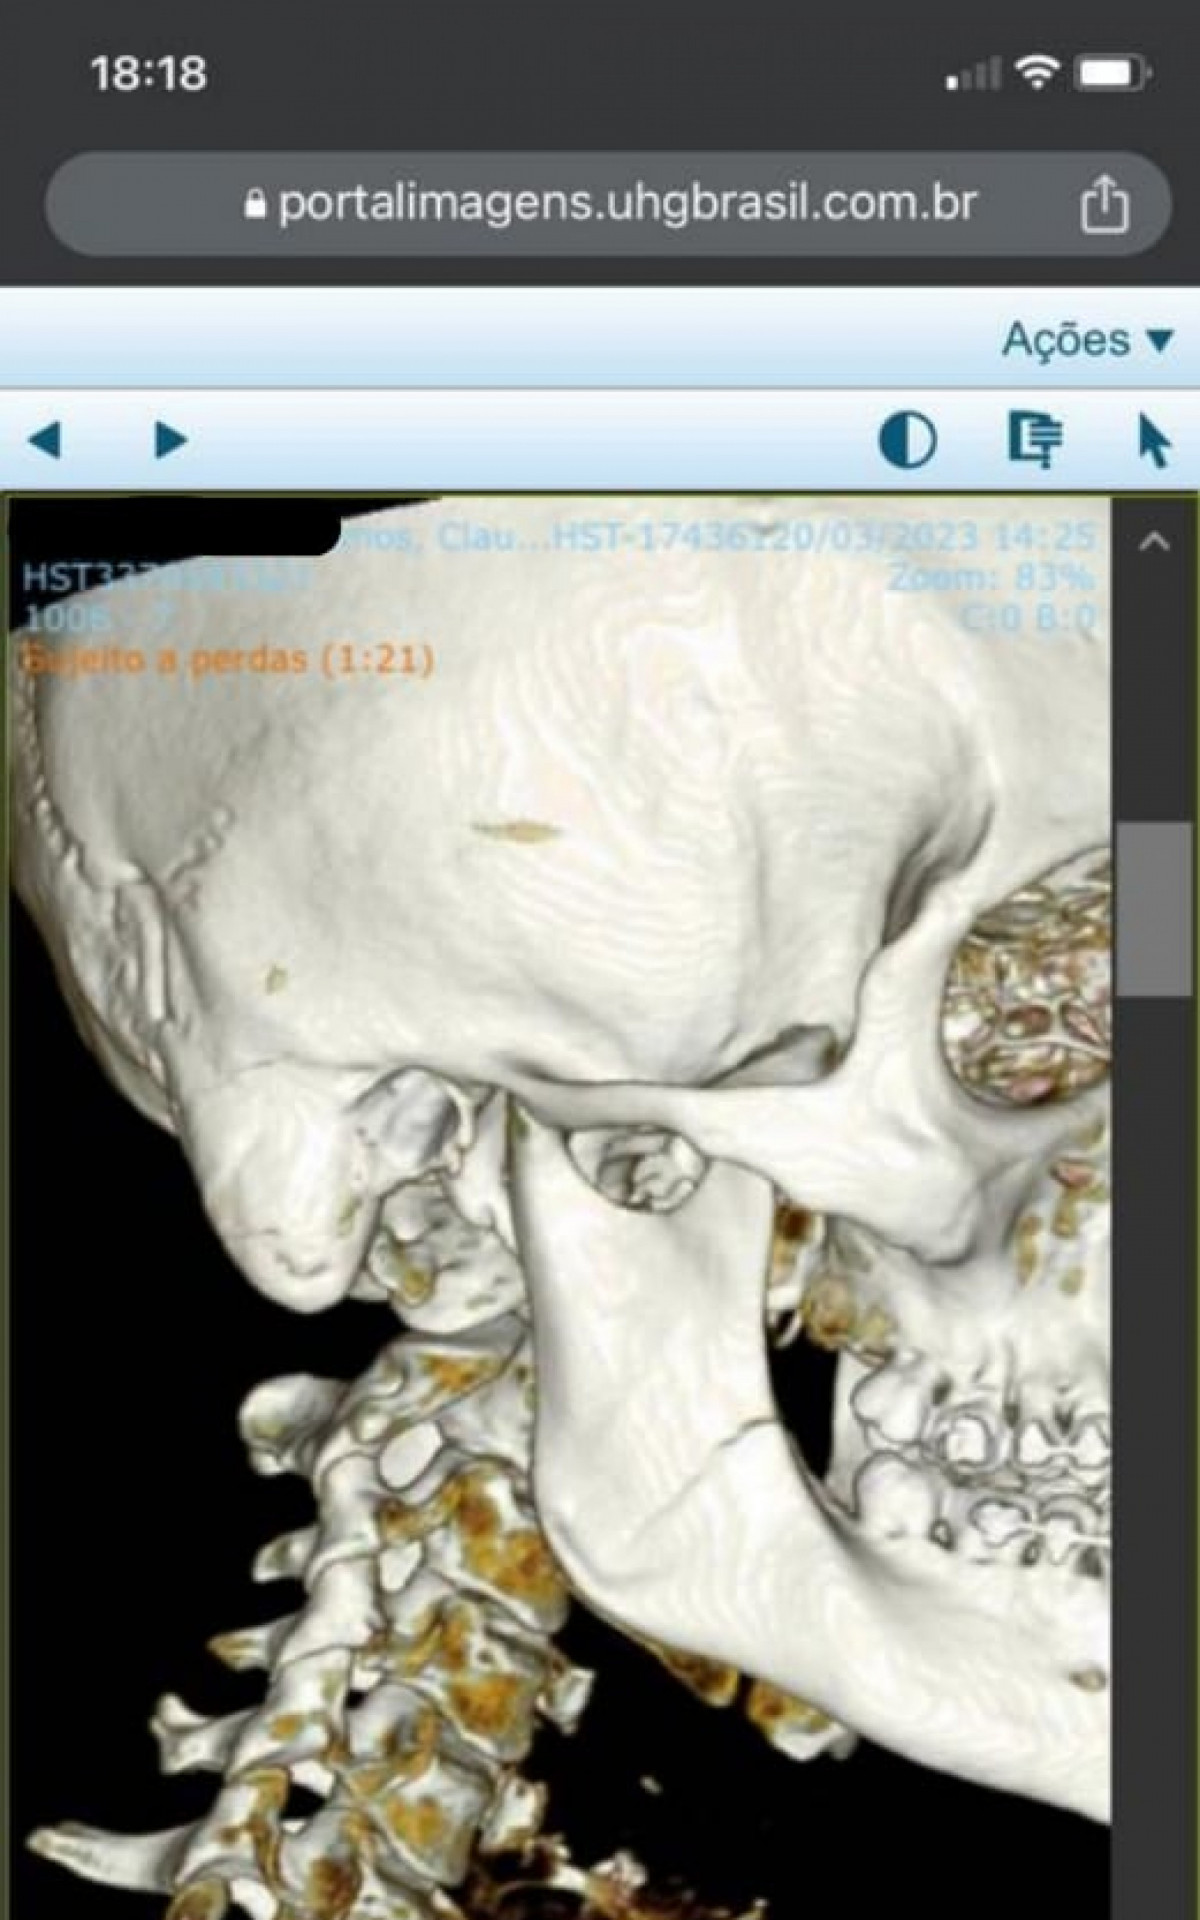

Tomografia de Cláudio Ramos confirma fratura no maxilar após agressões - Foto: Arquivo pessoal

Tomografia de Cláudio Ramos confirma fratura no maxilar após agressõesFoto: Arquivo pessoal

Rio - O torcedor do Vasco Cláudio Ramos, de 30 anos, foi agredido por quatro torcedores do Flamengo quando estava a caminho do Clássico dos Milhões, disputado no último domingo (19), no Maracanã, pela semifinal do Campeonato Carioca. Após levar golpes no rosto, ele passou por exames no hospital que confirmaram fraturas nos dois lados do maxilar e terá que passar por uma cirurgia de emergência.